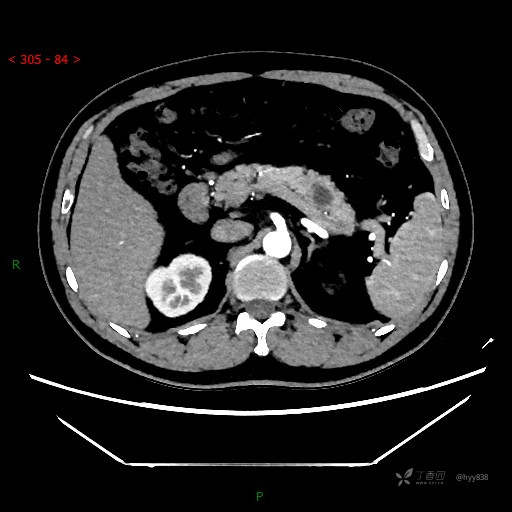

增强动脉期